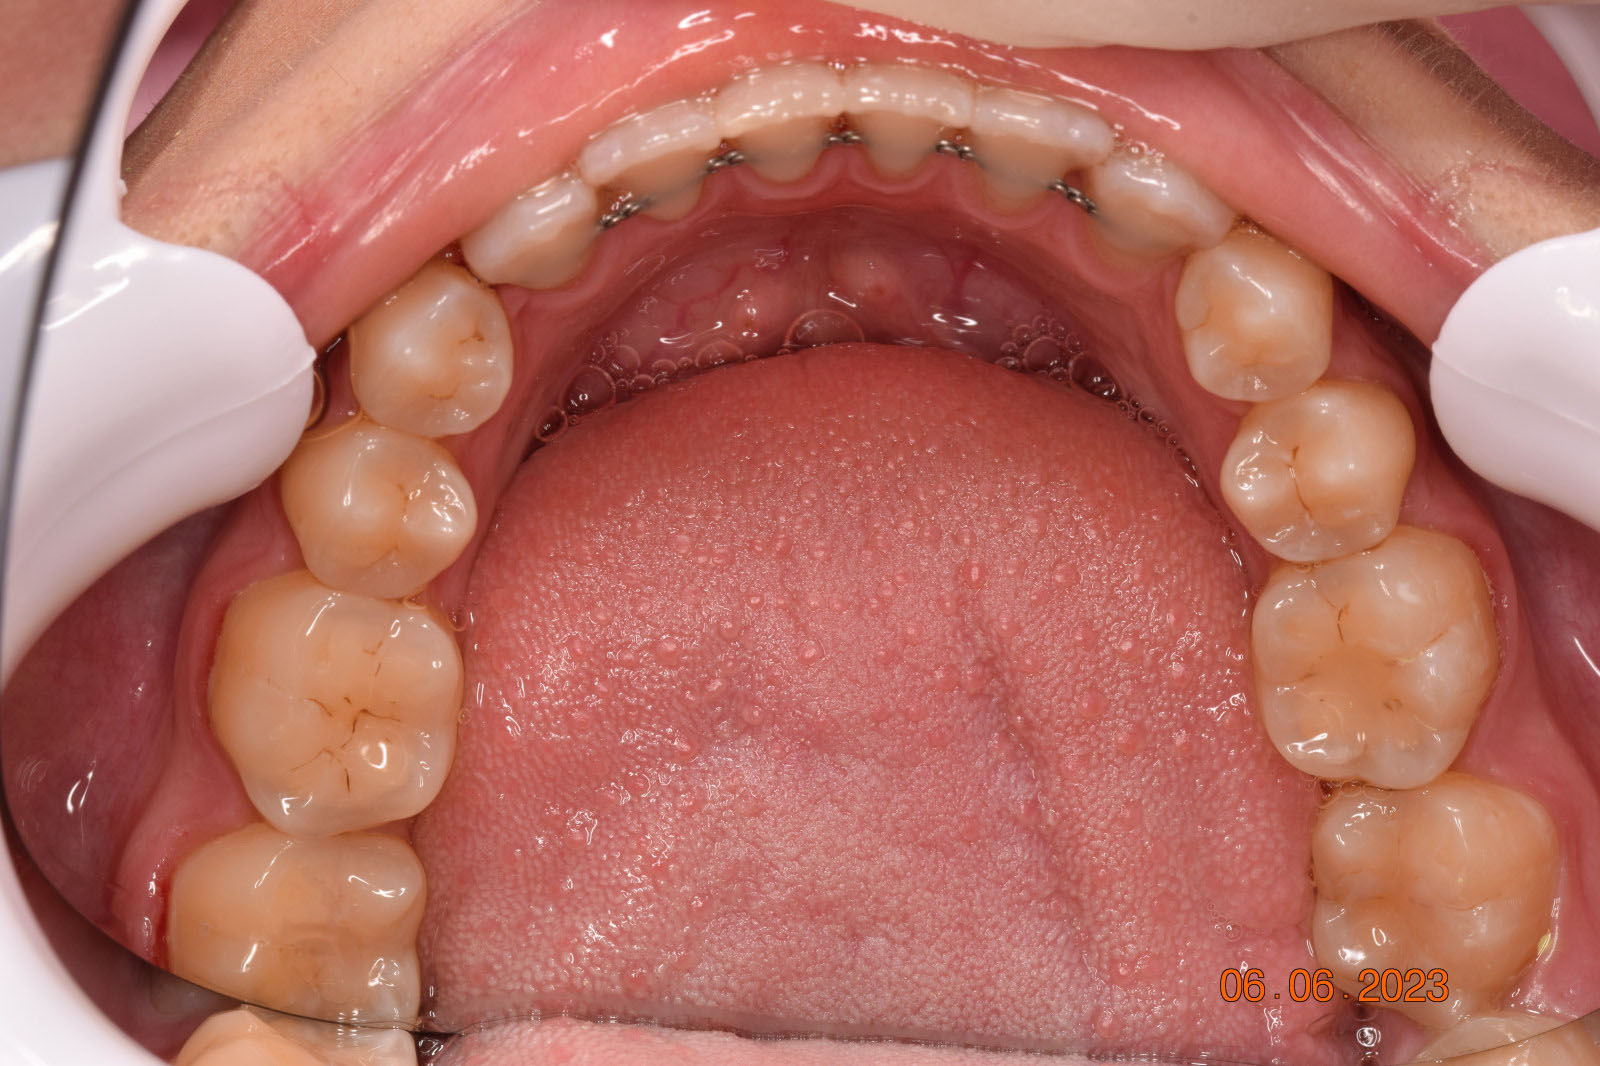

A 27-year-old female patient presented with class III malocclusion, 15 mm crowding in the upper arch, an anterior open bite, a lateral crossbite, and a total ABO score of 29. Her facial profile was straight with a retrusive maxilla, and the upper and lower incisors were retroclined. An extreme lack of midface support was also noted, and the constricted dental arches resulted in a poor smile width and dark buccal corridors. No myofunctional investigations were performed at the time, as they were initially considered unnecessary.

Adhering to the principles of Face First Orthodontics, the primary objective was to increase midface support by expanding the upper maxilla, fixing the cross bite, and aligning the teeth. Closing the open bite was a secondary objective.

The treatment began in 2017. Given the patient’s preference for less visible brackets, Damon Clear brackets were selected. High torque upper cuspids and low torque upper incisors were chosen to offer the best torque control for upper arch development. For the lower arch, there were no alternative bracket configurations available. Bite turbos were applied to the upper second molars.

The teeth are in a very good position and the bone has reshaped.